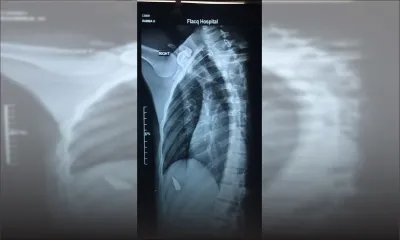

Actualités Actualités Waylann Margotton, 11 ans, décède en Inde : sa mère Marjorie : «C’est un véritable cauchemar»